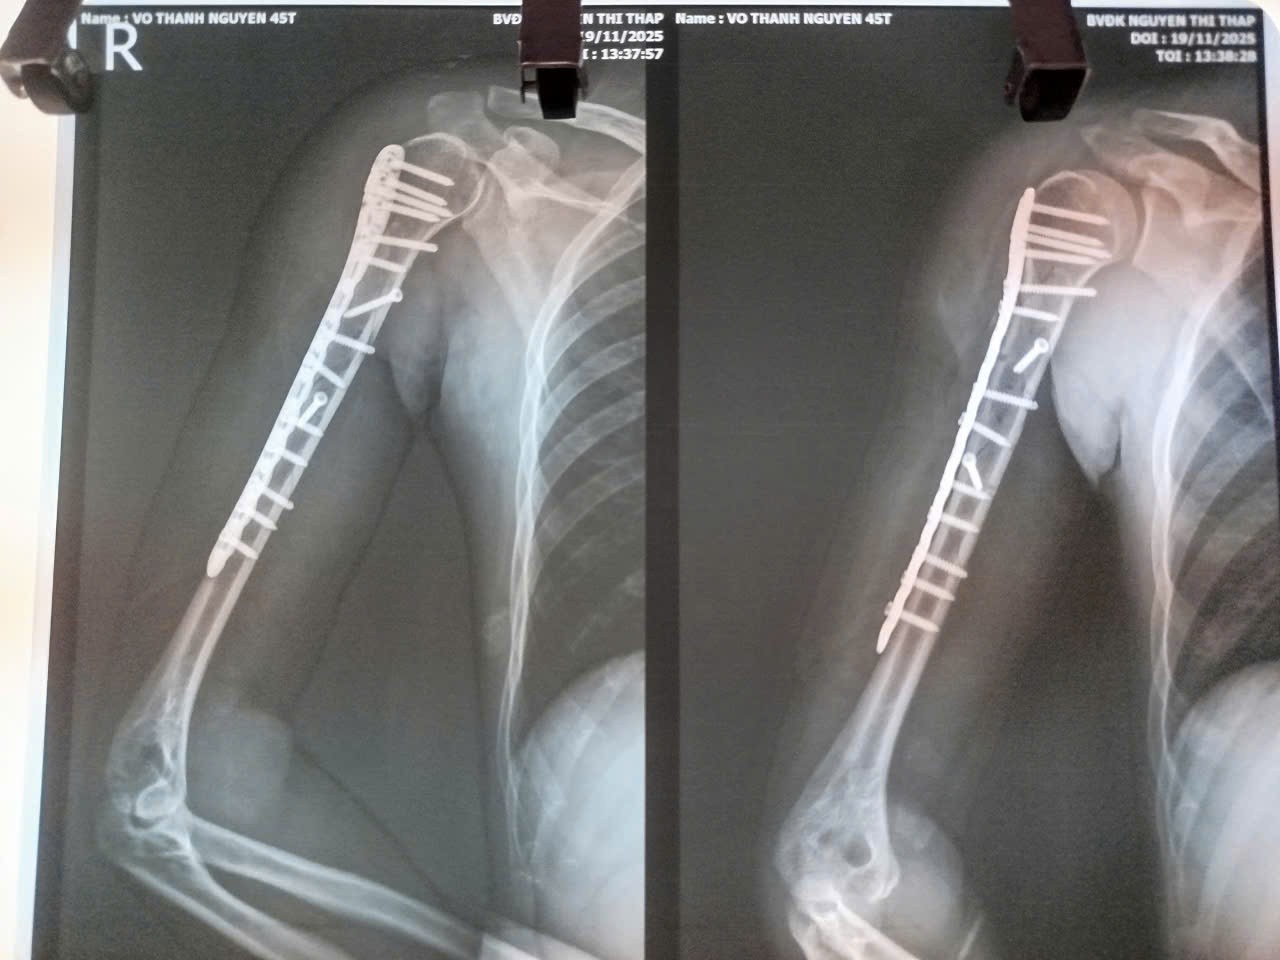

Tại khoa Cấp cứu, bệnh nhân được cố định tạm thời, chụp X-quang và xác định gãy nát phức tạp nhiều mảnh 1/3 trên xương cánh tay phải – một dạng gãy hiếm gặp, thường do lực xoắn mạnh gây ra. Sáng cùng ngày, ê-kíp bác sĩ Chấn thương Chỉnh hình tiến hành phẫu thuật kết hợp xương.

Ảnh chụp Xquang sau phẫu thuật